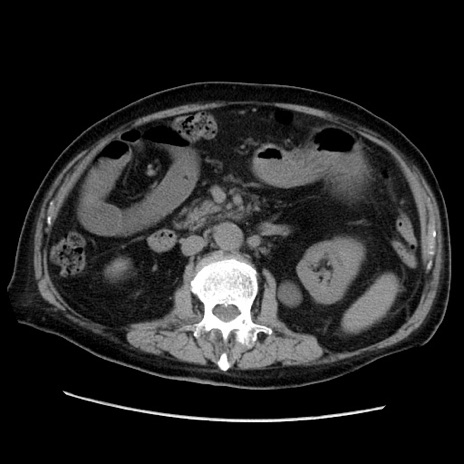

冠状断像

症例21(横断像)

【症例】70歳代男性

【主訴】腹痛

【現病歴】肝硬変・肝細胞癌にてかかりつけの方。約9時間前に食後より腹痛出現。症状が徐々に増悪し、嘔吐出現したため来院。

【既往歴】肝硬変、肝細胞癌(RFA、TACE後)

【身体所見】意識清明、表情苦悶様、BT 36℃、BP 129/78mmHg、P 88bpm、SpO2 97%(RA)、右上腹部から心窩部にかけて圧痛あり、反跳痛なし、筋性防御あり。

【データ】WBC 5800、CRP 0.16